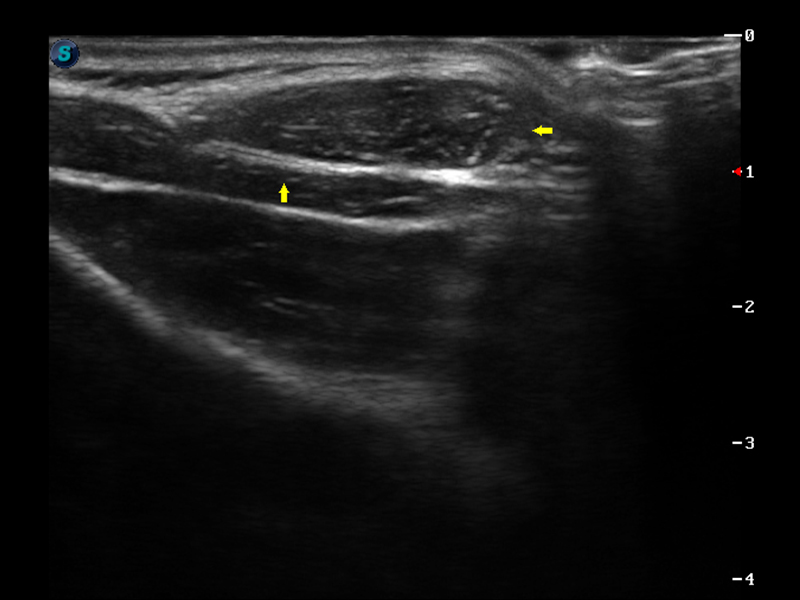

S9便携式彩色多普勒超声诊断仪是16877太阳集团研发的高端便携彩超设备,外观设计新颖、产品性能卓越。S9在便携超声领域采用了突破传统的触摸屏交互设计,并以先进的软件硬件技术和设计理念,为您带来清晰的图像质量、稳定的工作性能和便捷的操作体验。

μ-Scan微米成像

实时宽景成像